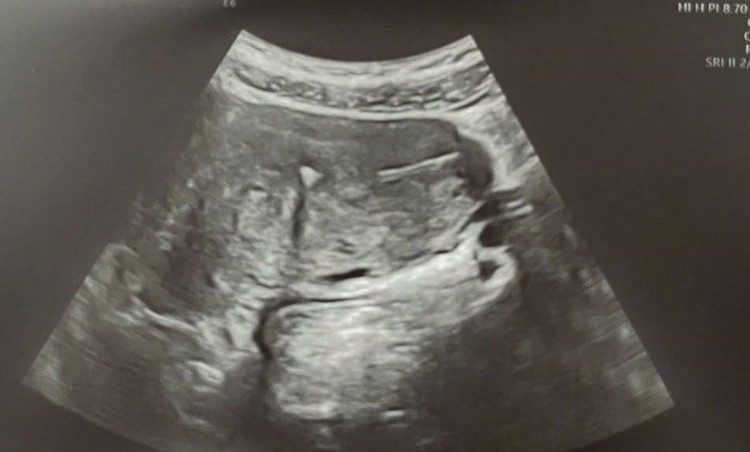

Vòng cắm sâu vào tử cung - Ảnh BVCC

Theo bác sĩ Nguyễn Công Nguyên (Bệnh viện Bạch Mai), dụng cụ tử cung có thể di chuyển xuyên thủng tử cung với tỉ lệ từ 1,3 - 1,6/1.000 lần đặt.

Sau khi xuyên qua tử cung, dụng cụ tử cung có thể rơi vào ổ bụng tự do hoặc nằm trong khung chậu, hoặc có thể xuyên thủng tiếp vào các cấu trúc lân cận như bàng quang, đại tràng, ruột non và hình thành các đường rò tử cung - bàng quang hoặc tử cung - ruột...